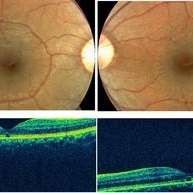

Central Areolar Choroidal Dystrophy

Central Areolar Choroidal Dystrophy

May 4 2021 by Priya Rasipuram Chandrasekaran, MBBS, DO, DNB, FRCS

Fundus photo of a 34-year-old male showing bilaterally symmetrical atrophy of retinal pigment epithelium (RPE) and choriocapillaris involving the fovea and highlighting the underlying large choroidal vessels. OCT macula shows atrophy of the outer retinal layers up to the external limiting membrane along with thinning of RPE and Bruch's membrane complex. Rosette - like hyperreflective structures causing retinal elevation at the border of atrophic area (yellow arrows) are seen categorizing this into stage 4 disease.

Condition/keywords: central areolar choroidal dystrophy (CACD)